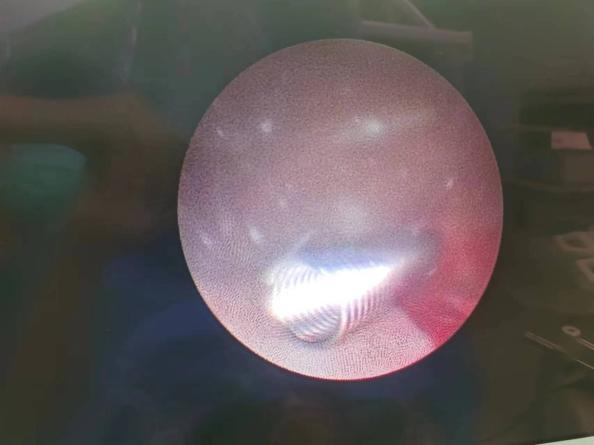

镜下见金属支架的置入过程

我院泌尿外科团队通过精准定位,测量出输尿管狭窄段的长度,将适合长度的记忆金属支架,经人体自然通道无创置入患者输尿管狭窄段。注入65℃热水后,镍钛合金支架成功膨胀,锚定于狭窄处,输尿管再度恢复通畅。术后第二天,患者便能下床活动,手术获得成功。

置入新型记忆金属支架后扩张效果良好